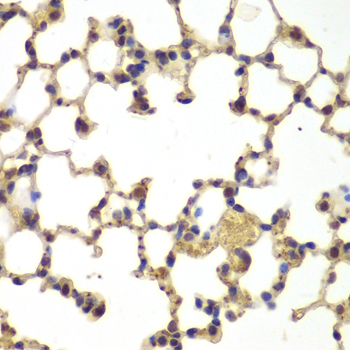

Immunohistochemistry of paraffin-embedded mouse lung using NFKB1 antibody at dilution of 1:100 (40x lens).